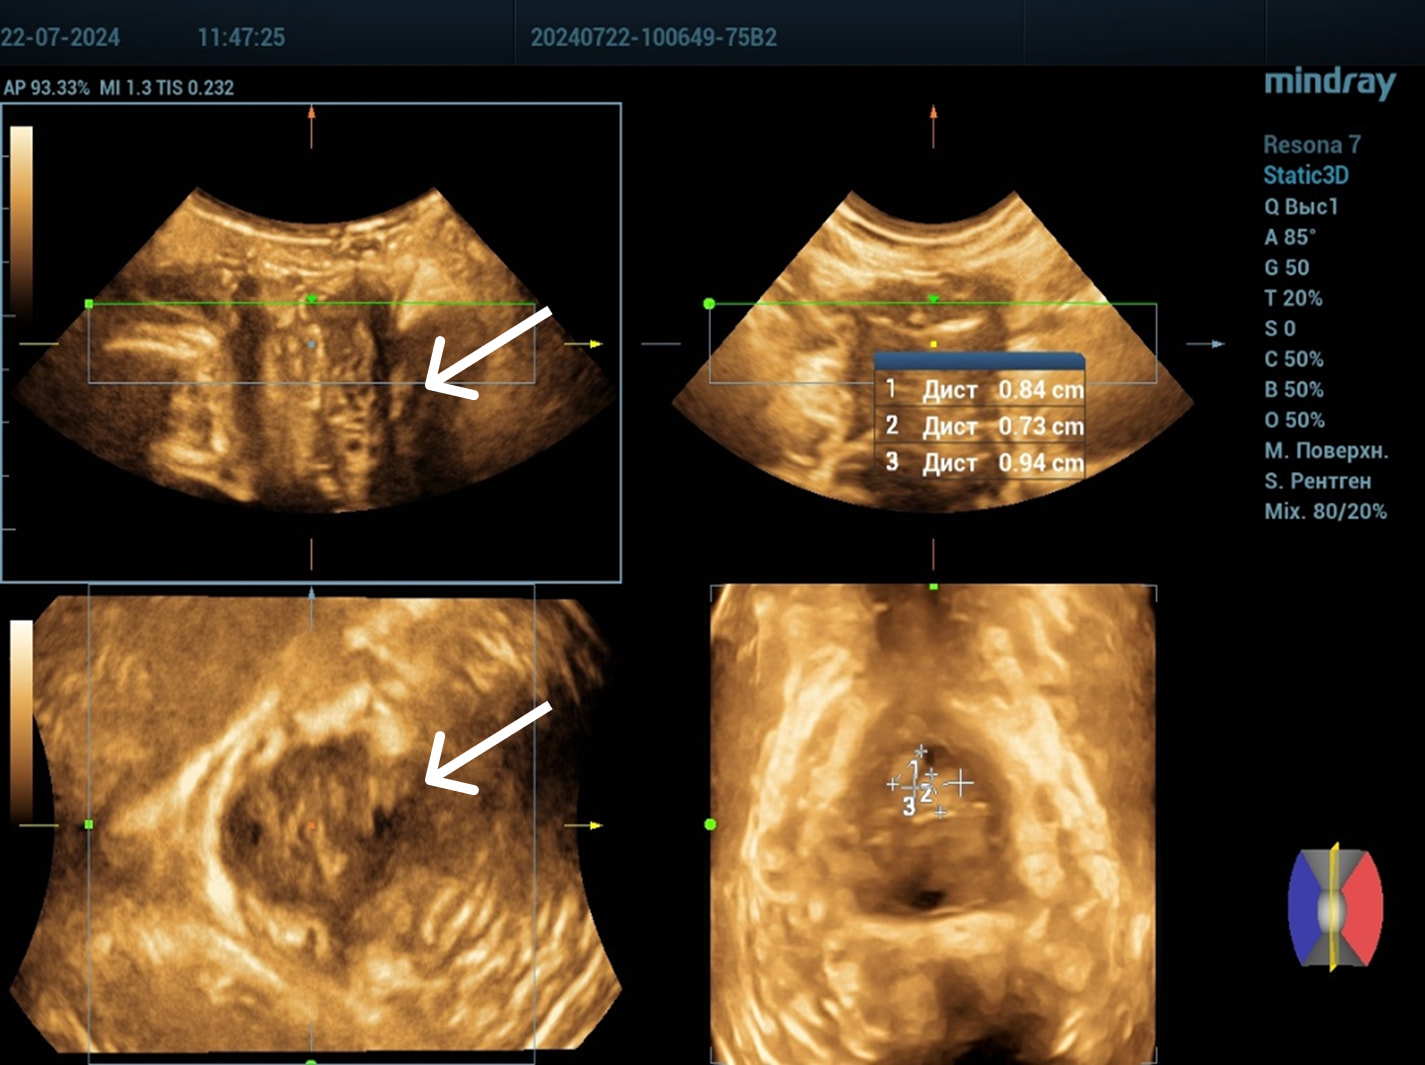

Осмотр: периуретрально визуализируется мягко-эластичное образование размерами 0,5×0,5 см.

Диагноз: хронический цистит (посткоитальный). Дистопия уретры. Опущение передней стенки влагалища I степени. Состояние после периуретрального введения геля на основе гиалуроновой кислоты.

Правильный ответ: Нет, достаточно консервативного лечения.